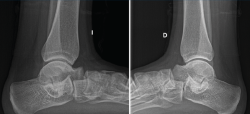

Figura 1. Segundo caso: coalición tarsal talocalcánea sinostótica bilateral. Pie derecho. Tomografía axial computarizada y radiografía.

Segundo caso (Figura 7)

Se trata de una paciente mujer de 18 años de edad, higienista dental, sin antecedentes patológicos de interés, que presenta pies planos valgos bilaterales dolorosos, el derecho de 23° y el izquierdo de 21° de valgo, por sinostosis calcaneoastragalina media en ambos pies. En ella observamos básicamente una clínica de dolor en el seno del tarso, con déficit de movilidad de la articulación subtalar en ambos pies. Se realiza estudio mediante radiografías de los pies y los tobillos en carga y TAC de ambos pies (afectación bilateral). Radiológicamente, las articulaciones tibioperoneoastragalina y subtalar están preservadas. Se diagnostica de coalición tarsal de tipo 4 de la clasificación de Rozansky(26). El balance articular es de: flexión = 45°; extensión = 20°; inversión = 0°; eversión = 0°. La escala de la AOFAS para el tobillo derecho presentaba una puntuación de 62 (20-37-5). Los ángulos radiológicos iniciales son: Moreau-Costa-Bartani interno = 141°; declinación talar = 18,4°; Meary = 6,3°; Kite = 25,6°; taloescafoideo = 48,3°.